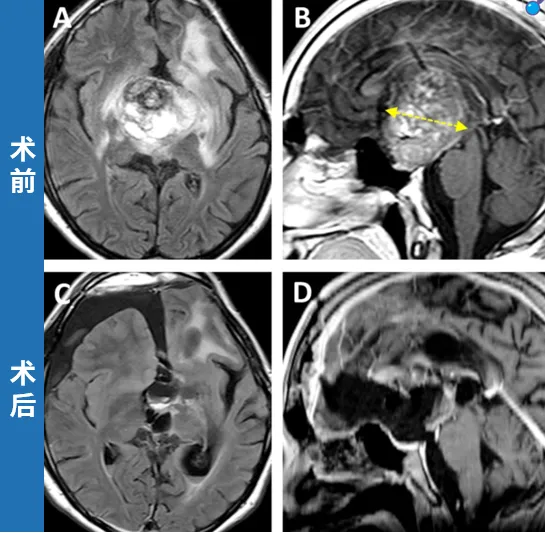

案例四:下丘脑胶质瘤

16岁的丹尼尔,4岁时确诊为下丘脑毛细胞型星形细胞瘤,第一次术后因肿瘤残留接受了多轮化疗,复查时发现肿瘤复发,同时出现全垂体功能减退和严重左眼视力下降,几近失明。复查头颅MRI显示鞍内、鞍上存在巨大占位,并延伸至左侧海马旁回及侧脑室。INC巴特朗菲教授接诊后评估认为,手术切除是唯一合理的治疗方式。最终,肿瘤获得近全切,视交叉、视束、垂体柄及下丘脑功能均得以保留。